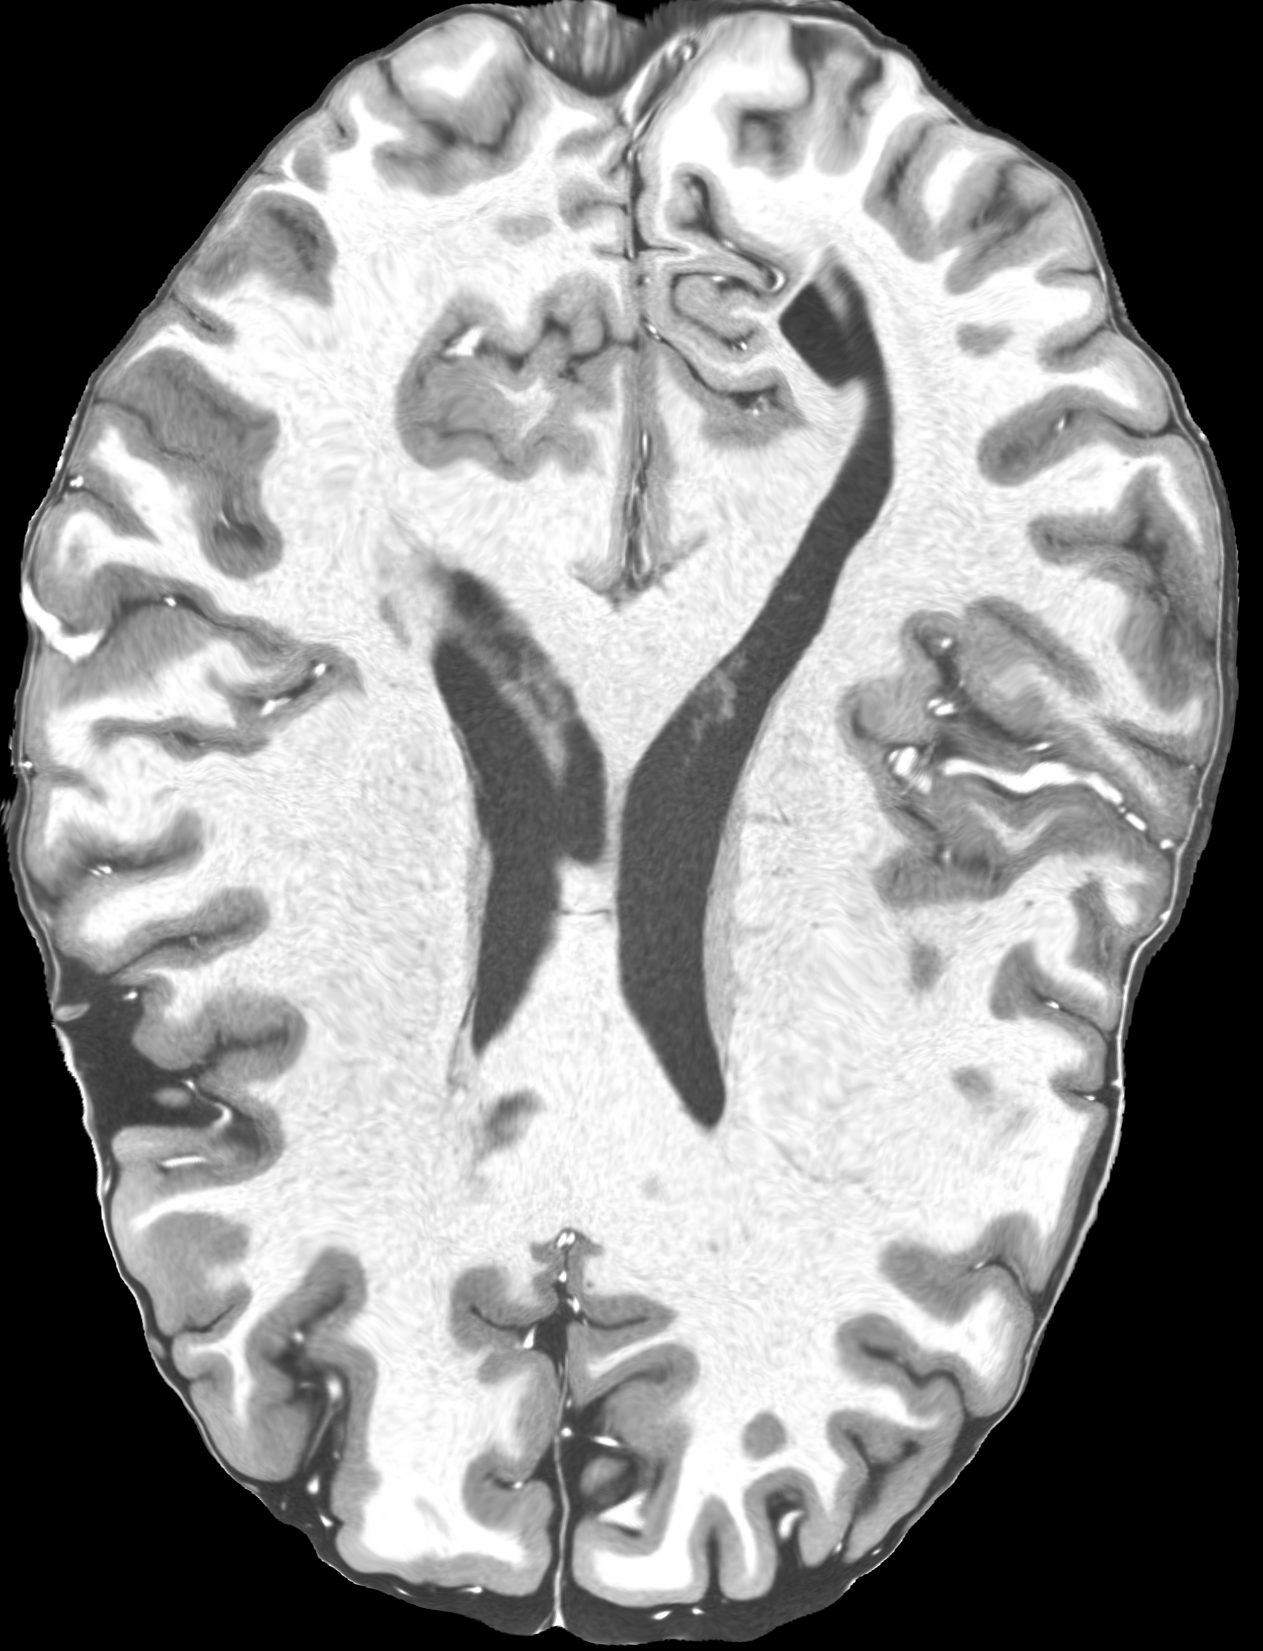

4.2 Registration to a 100 micron ex-vivo brain MRI volume

To showcase the efficacy of our method on real large scale images, we register a 250 in-vivo MRI image (Lüsebrink et al., 2017) to a 100 ex-vivo FLASH human brain volume (Edlow et al., 2019). This represents an inverse problem with more than 11.2B optimizable parameters (compared to 20M for clinical datasets), or 44.8GB of GPU memory. The entire problem does not fit on most GPUs, necessitating distributed multimodal registration. We optimize a composite transform - affine followed by a diffeomorphic mapping; details can be found in Section E.1. Multimodal deformable registration took 58 seconds on 8 NVIDIA A6000 GPUs, which is unprecedented at this resolution. Fig. 6 shows qualitative results, highlighting the ability to register highly detailed structures such as cerebellar white matter; these structures are not visible at macroscopic scales. The resultant advantages of performing registration at this scale can allow researchers to characterize the neuroanatomy at microscopic resolutions and allow morphometric analysis of cortical layers and subcortical nuclei among other structures.